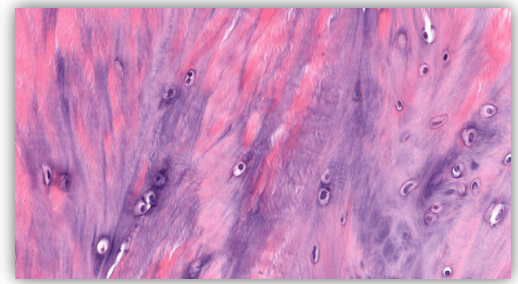

Identify

A

Perfectly

5

Q

Mammalian cartilages are typically ______